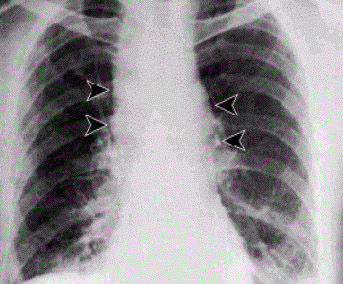

1. ÁNTRAX PULMONAR

1. SÍNTOMAS

1. Tos

1. Estornudos

1. Fiebre

1. Escalofríos

1. Dolores en el precho

1. Problemas severos al respirar

1. Shock

1. Taquicardia